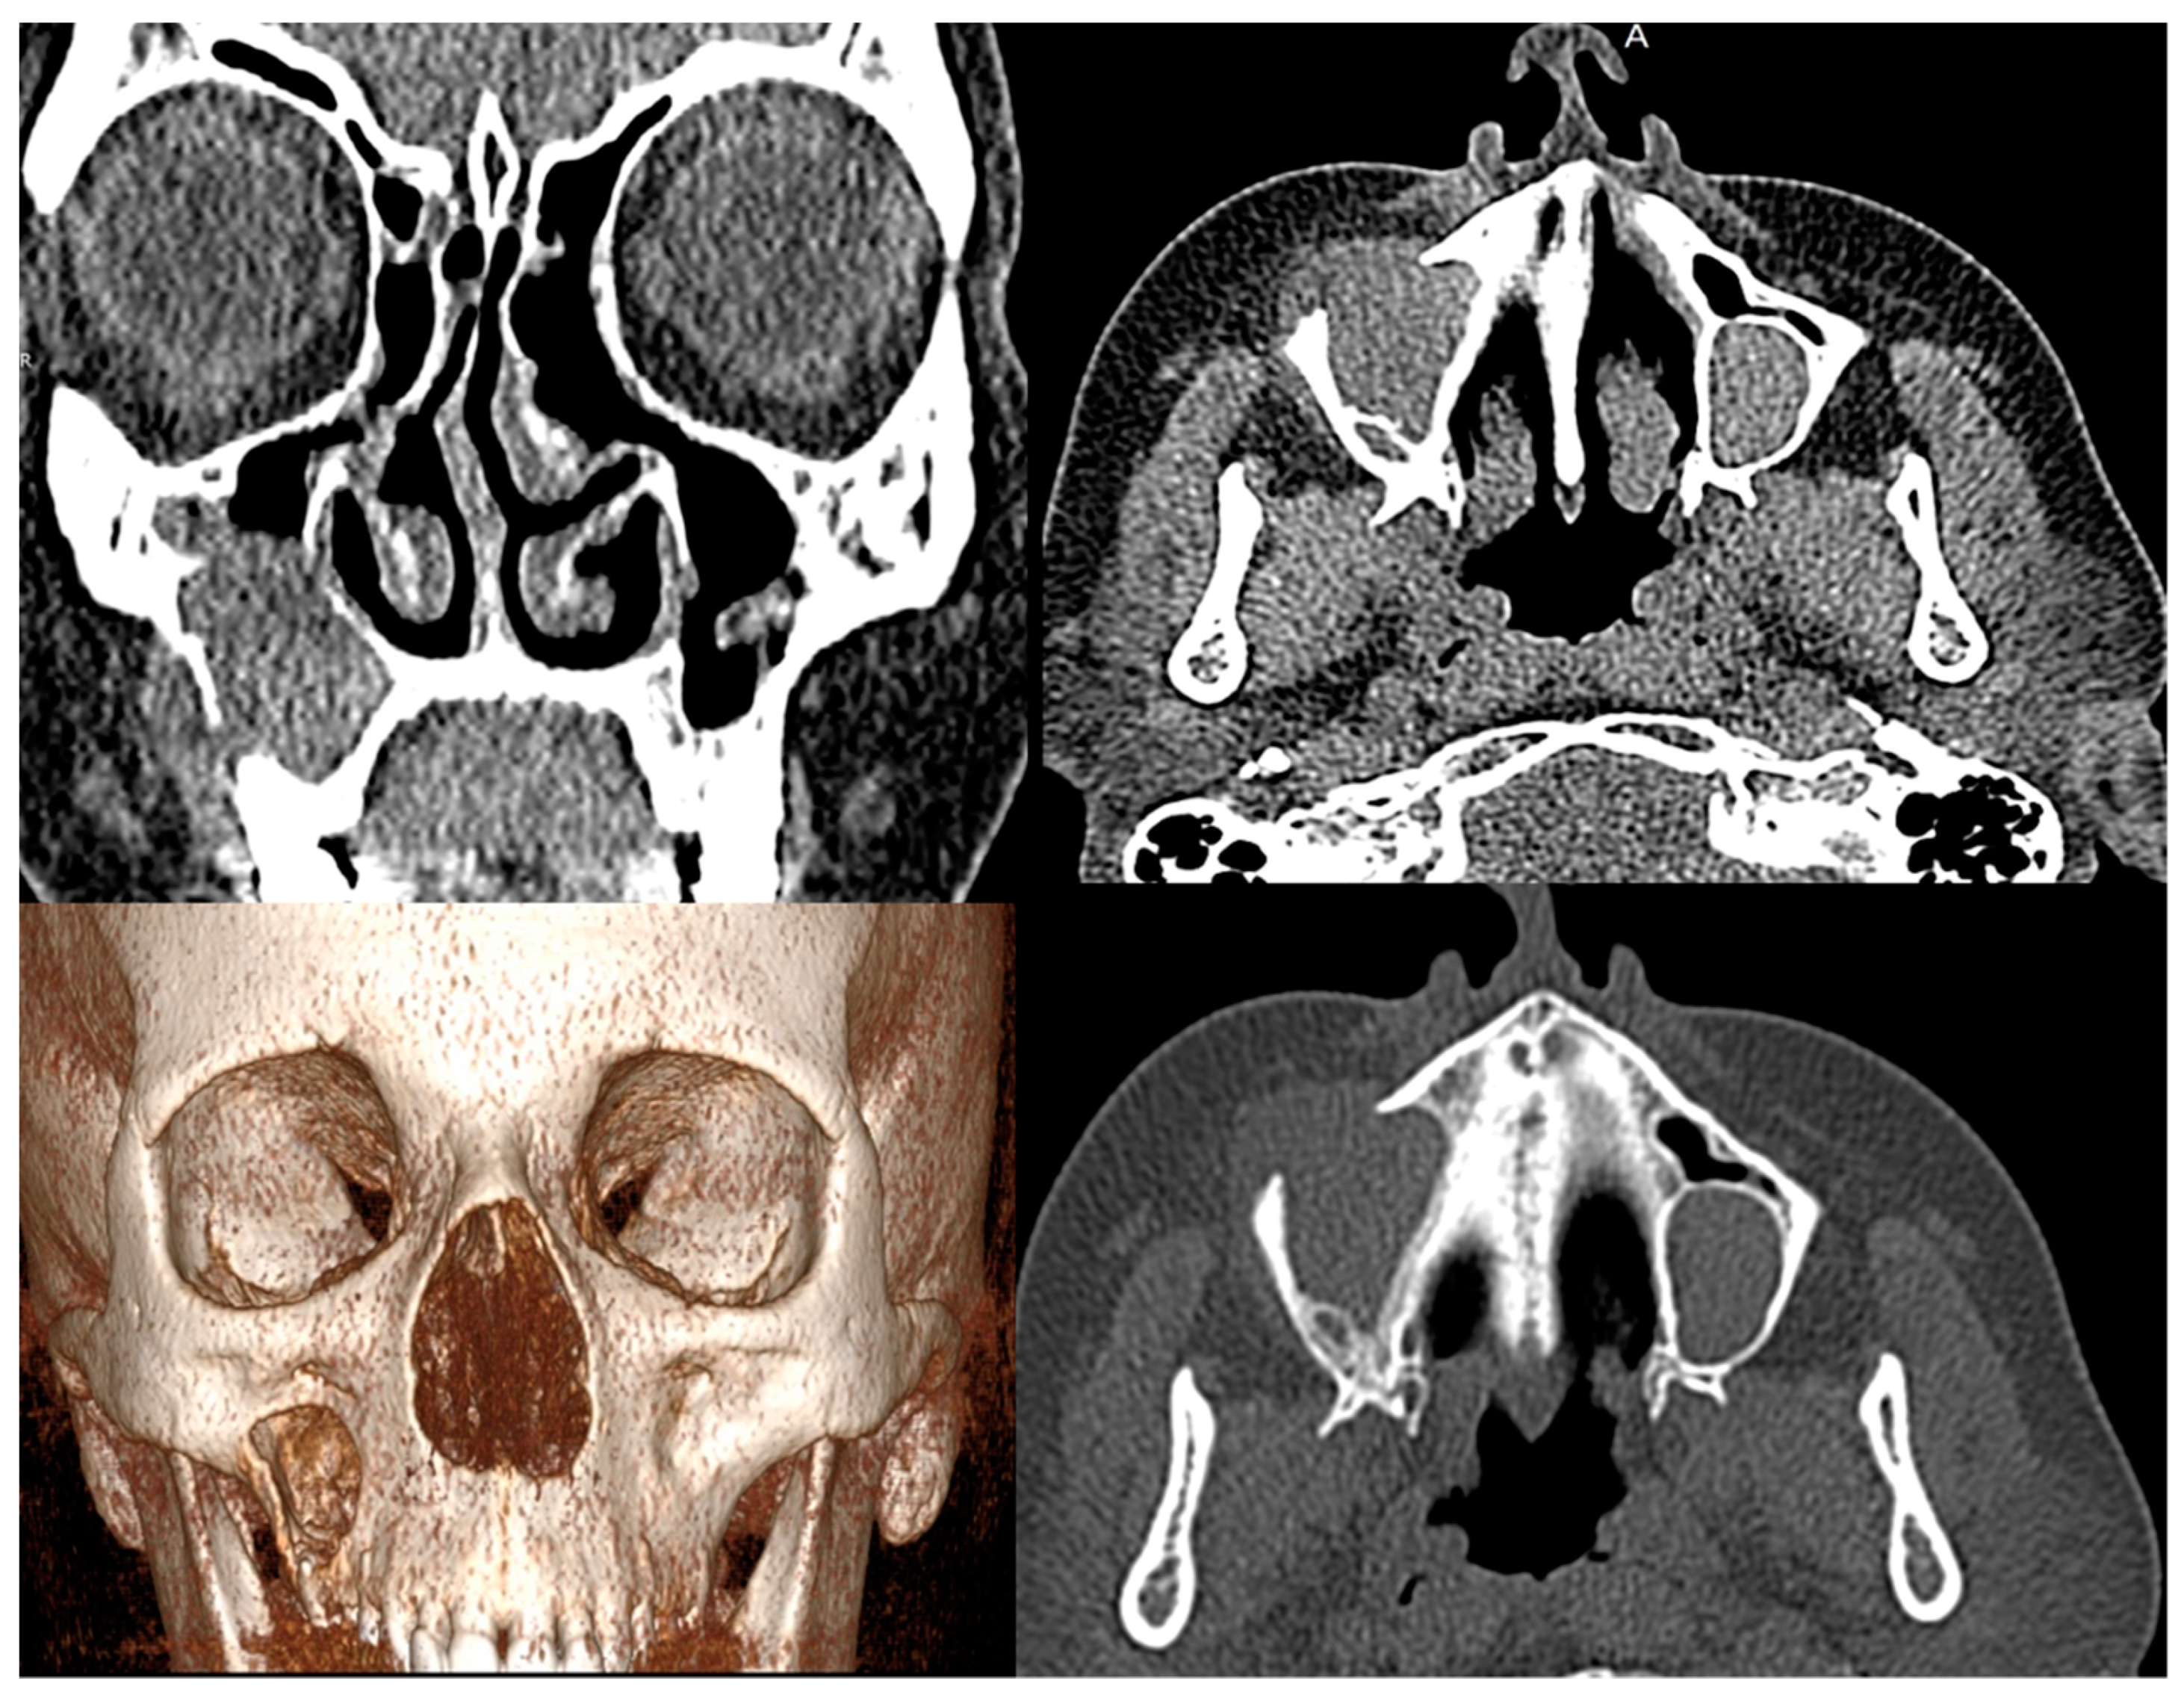

- Fujita, A.; Sakai, O.; Chapman, M.N.; Sugimoto, H. IgG4-related disease of the head and neck: CT and MR imaging manifestations. Radiographics 2012, 32, 1945–1958. [Google Scholar] [CrossRef]